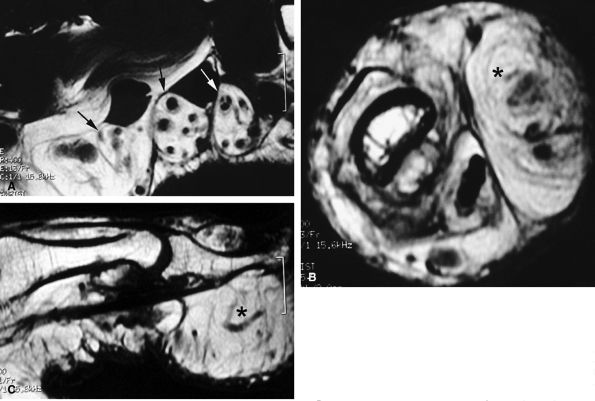

FIGURE 11.67 ● Intraneural ganglion. Axial (A and B) and coronal (C) T1-weighted images of a ganglion (asterisk) infiltrating the medial proper digital nerve (arrows).

images show intratendinous extension of the cyst with peripherally displaced thin tendinous walls (Fig. 11.66). Tenosynovitis is commonly associated at the level of the wrist. A painful cyst may be due to extrinsic nerve compression or, rarely, intraneural infiltration of a proper digital nerve (Fig. 11.67).137 Intraosseous ganglions in the phalanx have also been reported.138